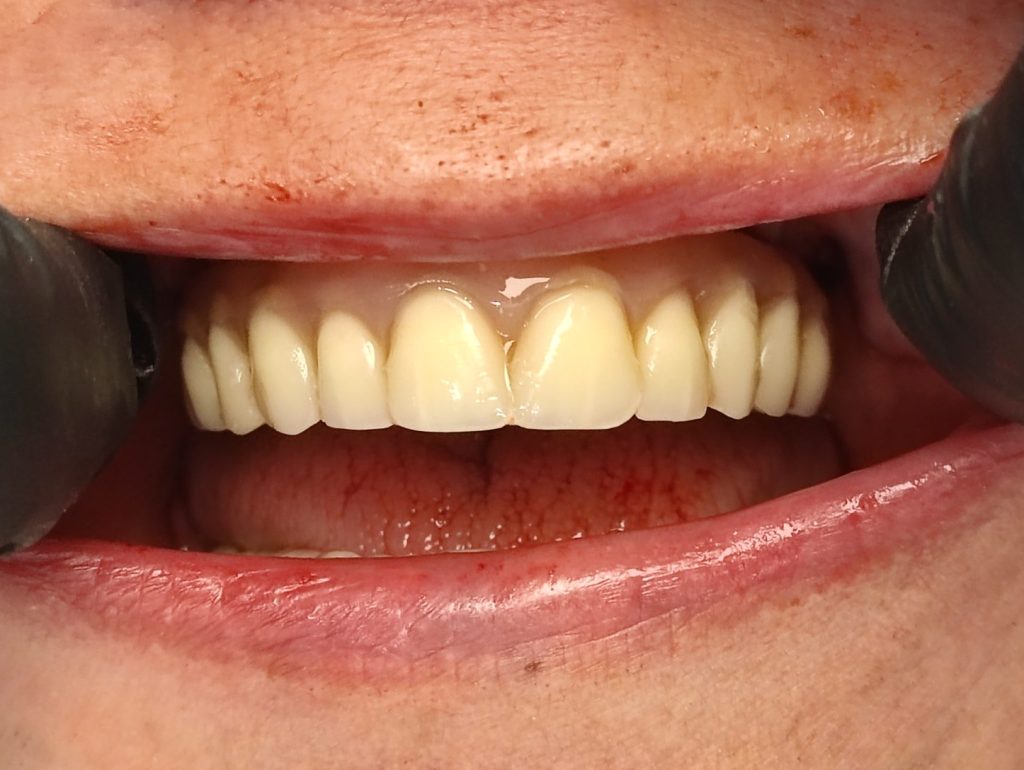

A végleges All-on-4 híd gyönyörűen illeszkedik az ínyhez, formája és színe teljesen természetes hatású. A kerámiahíd könnyen tisztítható és rendkívül strapabíró, így megfelelő szájhigiénia mellett akár élethosszig is megőrizheti funkcióját és esztétikumát.

Végleges kerámia all-on-4 fix fogpótlás 3 hónapos kontroll után

Végleges kerámia all-on-4 fogpótlás 1 év elteltével